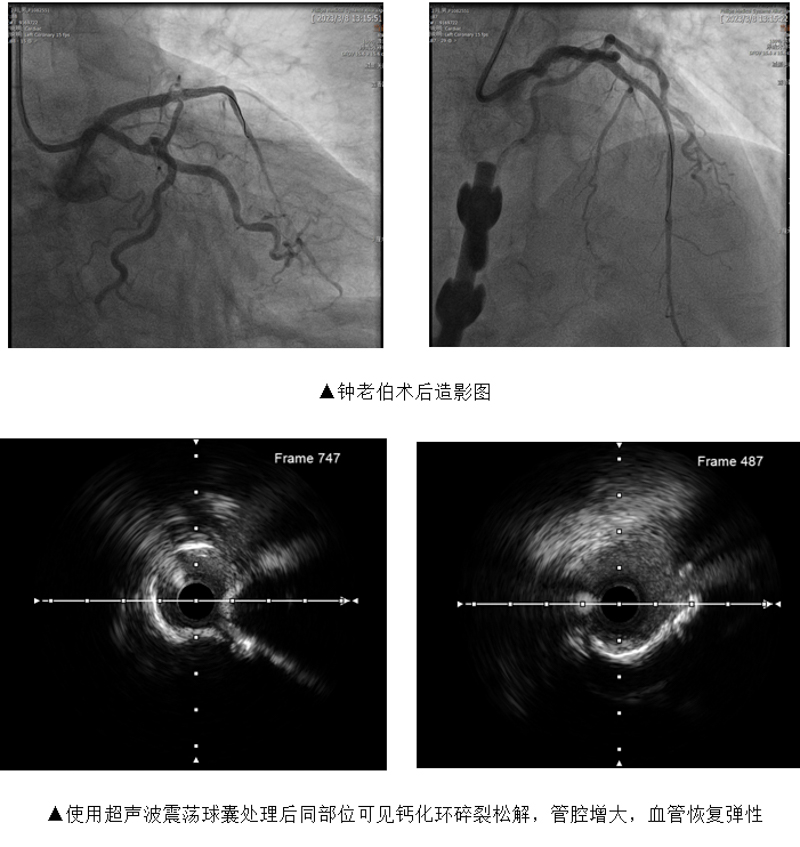

術中,心血管內科二病區副主任王勇在ECMO輔助下順利將導絲通過前降支閉塞病變處。正如術前評估,IVUS檢查提示該患者左主干、前降支、回旋支多處360°環狀鈣化并管腔嚴重狹窄,且患者血管存在不同程度迂曲及成角,如應用冠脈內旋磨等方法處理,冠脈穿孔、破裂風險陡增,因此使用IVL處理鈣化病灶是最優選擇。術者先后應用Shockwave 3.5×12mm沖擊波球囊分別于左主干-前降支、回旋支環狀鈣化病變處共計觸發8個周期的沖擊波鈣化斑塊碎裂術,經IVUS證實鈣化環多點碎裂松解效果滿意,血管充分預擴張后順利完成分叉病變的支架植入,手術取得圓滿成功。

柳州市人民醫院心血管內科二病區副主任王勇介紹,冠狀動脈嚴重鈣化并慢性閉塞病變介入難度大、風險高,預處理不佳或支架膨脹不全,極易造成支架內血栓或支架內再狹窄事件發生。像鐘老伯這樣,病變累及左主干、前三叉病變在過去只能選擇外科開胸進行冠脈搭橋手術,很多老年患者一般情況差,基礎疾病多,無法耐受麻醉及外科手術,不得不放棄治療。隨著介入醫學的高速發展,針對冠脈鈣化病變涌現出多種先進治療方案,如種類繁多的冠脈功能球囊、冠脈旋磨術、激光斑塊銷蝕術等,各有利弊,IVL通過超聲壓力波作用于冠脈內斑塊,在不損傷冠脈正常組織的前提下精準碎裂冠脈鈣化病灶,讓僵硬的血管恢復彈性,更因其操作相對簡單、安全性優異,預處理效果好,成為冠脈鈣化病變治療新方案。